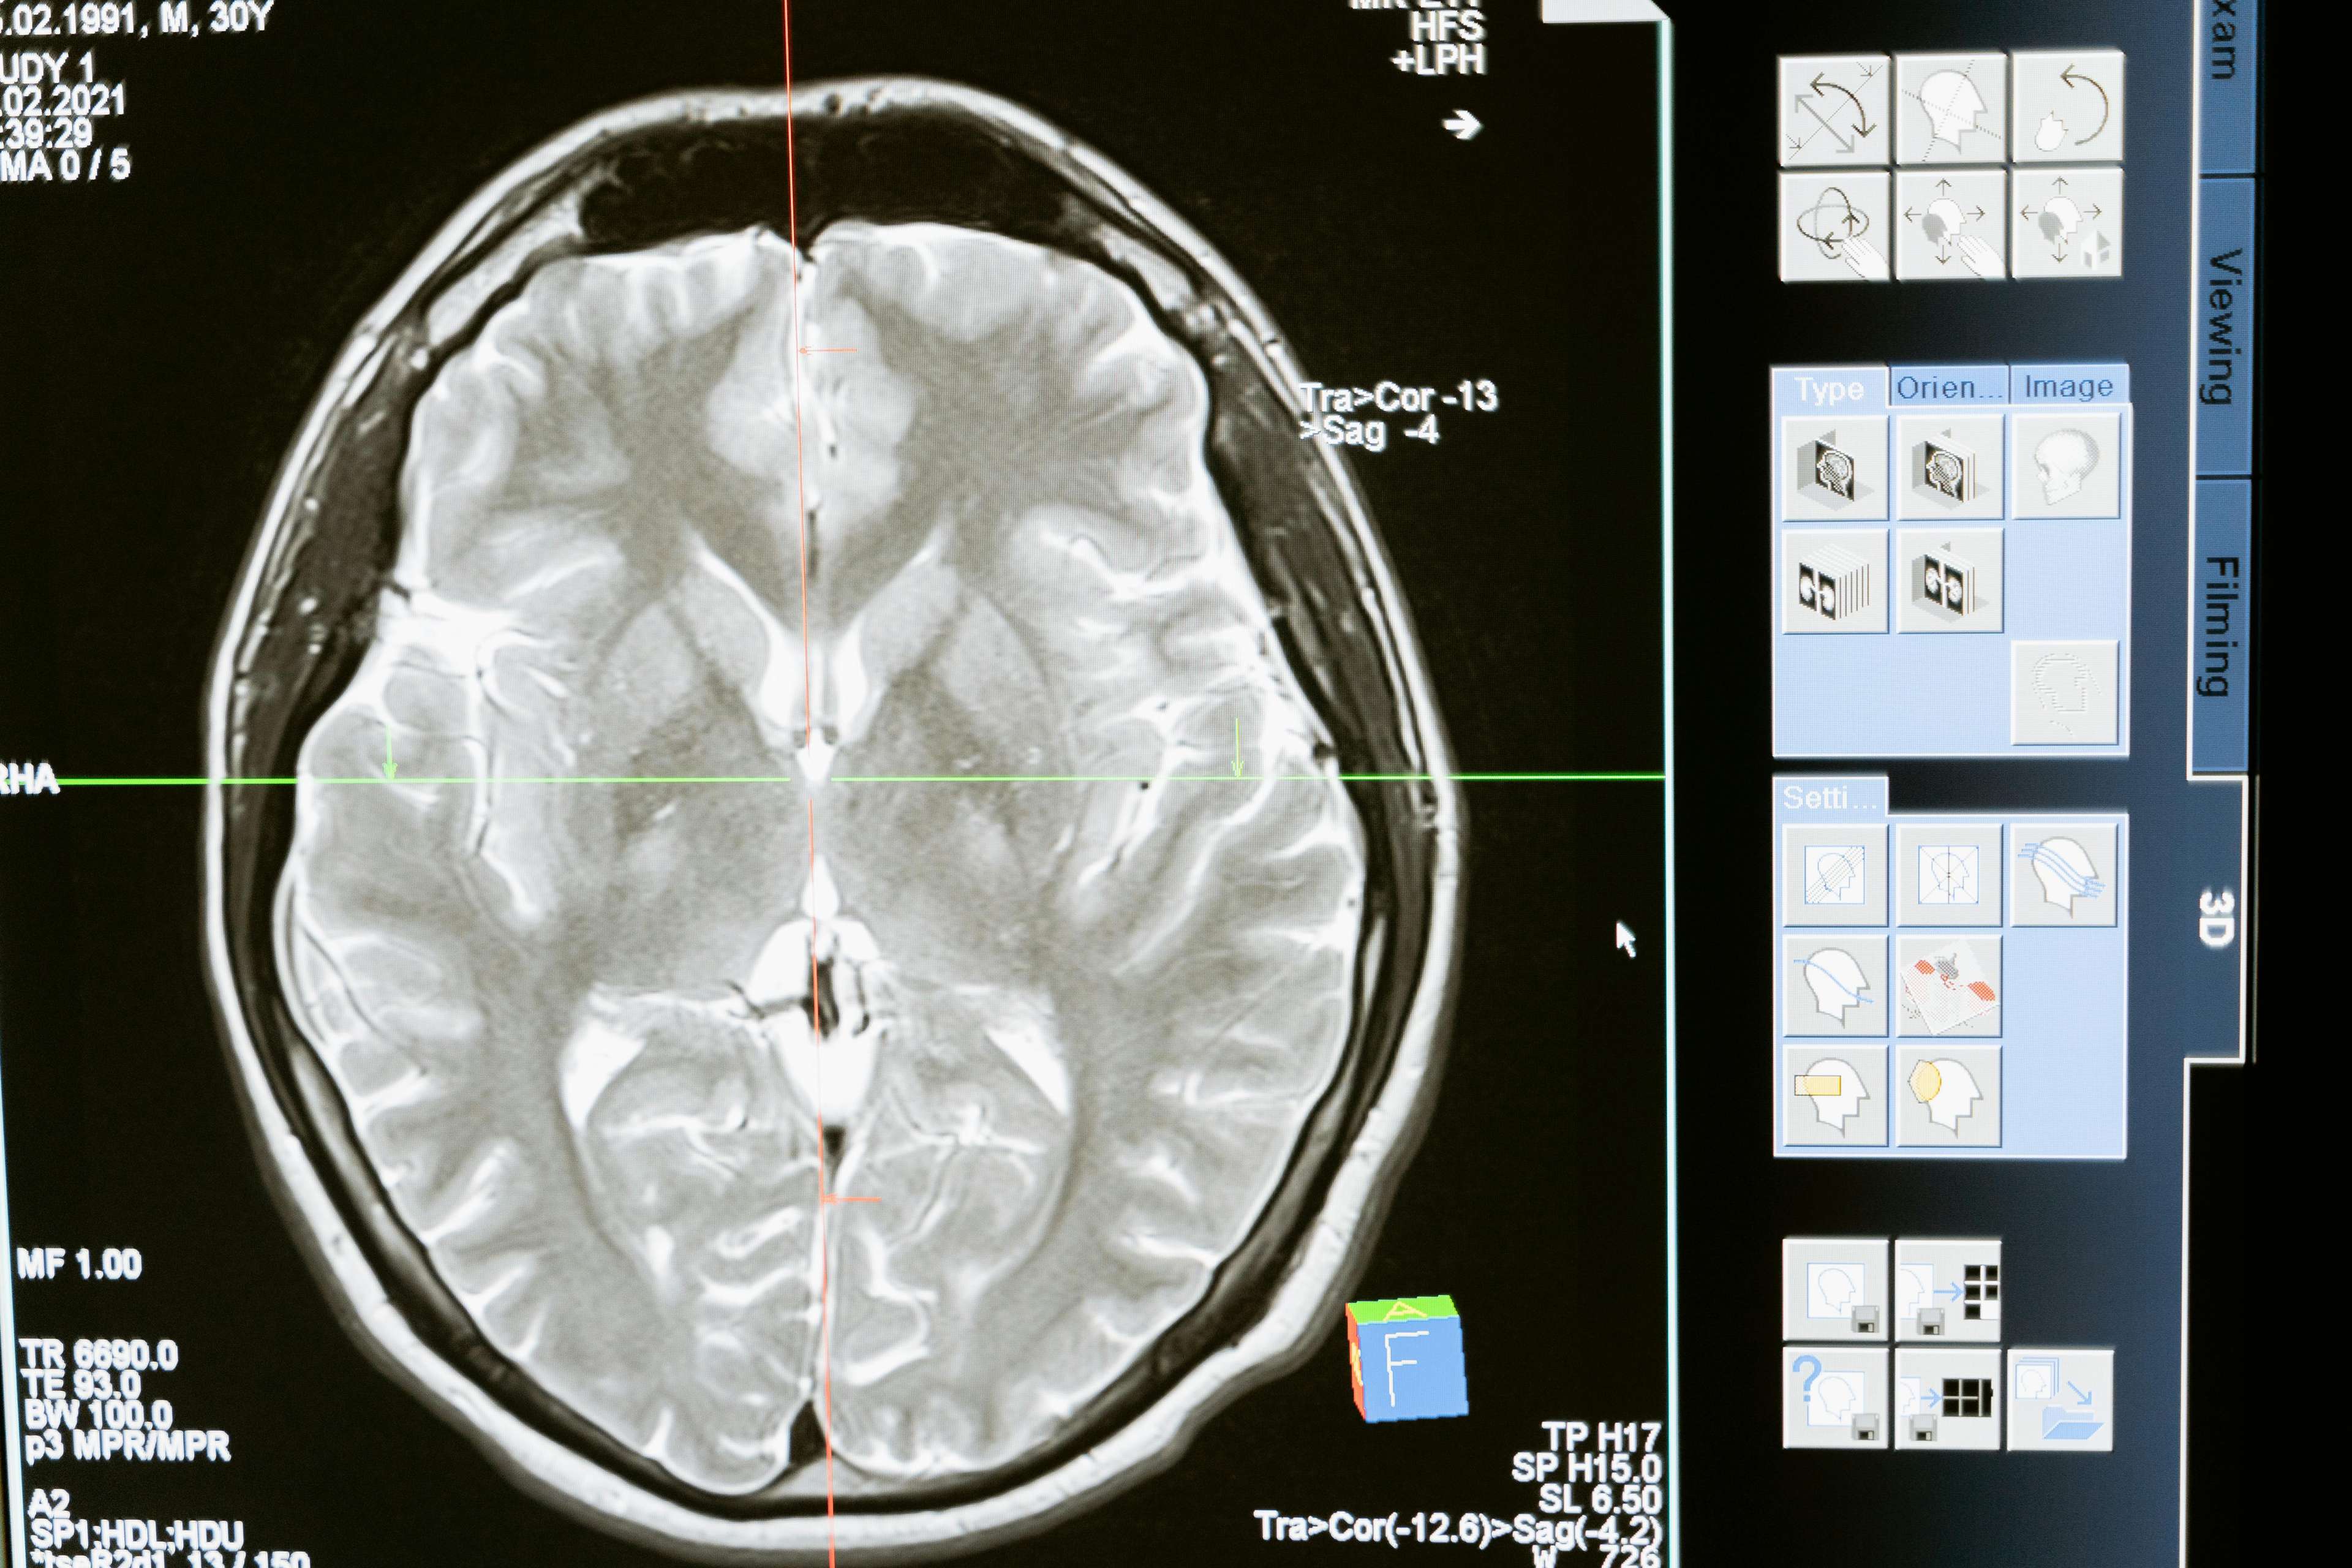

Ang DBS ay isang kirurhiko na pamamaraan na nagsasangkot ng pagtatanim ng isang aparato na nagpapadala ng mga de -koryenteng impulses sa mga tiyak na lugar ng utak, na epektibong "muling pag -rewiring" ang mga koneksyon sa neural na responsable para sa mga sintomas ng iba't ibang mga sakit sa neurological. Ang makabagong paggamot na ito ay naging instrumento sa pagpapagaan ng pagdurusa ng mga indibidwal na may mga kondisyon tulad ng Parkinson's disease, dystonia, obsessive-compulsive disorder (OCD), at epilepsy, bukod sa iba pa. Sa pamamagitan ng pag-target sa ugat ng mga kundisyong ito, ipinakita ng DBS na makabuluhang mapabuti ang paggana ng motor, bawasan ang mga panginginig, at pagandahin ang pangkalahatang kalidad ng buhay.

Kaya, paano ginagawa ng DBS ang magic nito. Kita mo, ang ating mga utak ay naka-wire sa isang masalimuot na network ng mga neuron na nakikipag-usap sa isa't isa sa pamamagitan ng mga electrical impulses. Sa mga indibidwal na may karamdaman sa neurological, ang mga impulses na ito ay maaaring magambala, na humahantong sa isang pagkasira sa komunikasyon at, sa huli, ang pagpapakita ng mga sintomas. Gumagana ang DBS sa pamamagitan ng pagtatanim ng isang aparato na nagpapadala ng mga de -koryenteng impulses sa mga tiyak na lugar ng utak, na epektibong "i -reset" ang mga koneksyon sa neural at pagpapanumbalik ng balanse sa maselan na ecosystem ng utak.